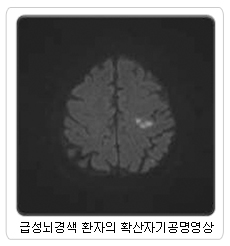

그러므로 위험인자인 고혈압, 심장질환, 당뇨병, 흡연, 고지혈증의 적극적인 치료로 뇌경색증을 예방하는 것이 중요합니다. 그럼에도 불구하고 뇌경색증이 발생했다면 가장 중요한 것은 빠른 시간 내에 치료를 시작하는 것입니다. 뇌조직은 혈액 공급이 막힌 후 3시간 이내에 혈액이 재공급되면 다시 살아납니다. 그러므로 급성 뇌경색증 환자의 치료는 시간과의 싸움입니다. 통상 증상 발생 후 3시간 이내라면 혈관을 뚫어주는 주사액을 정맥주사 하면 뇌경색이 풀리게 됩니다. 만약 3시간에서 6시간 사이라면 동맥 촬영술로 막힌 부위를 찾아내어 가는 도관을 이용해 막힌 부위까지 도관을 접근시켜 뚫어주는 방법을 쓰고 여의치 않을 때는 스텐트란 관을 설치하여 동맥에 혈류가 다시 흐르게 하면 뇌경색이 풀리게 되는 경우가 많습니다. 그러나 이 시간 때를 놓치면 약물주입으로 뇌출혈만 발생시키게 되어 적극적인 치료가 불가능합니다. 그러므로 뇌경색증 증상이 발견되면 조금도 시간을 지체하지 말고 이 같은 시술이 가능한 일정규모 이상의 병원으로 후송하는 것이 환자의 예후에 가장 중요합니다. 글∥송관영(서울의료원 신경외과 주임과장) |